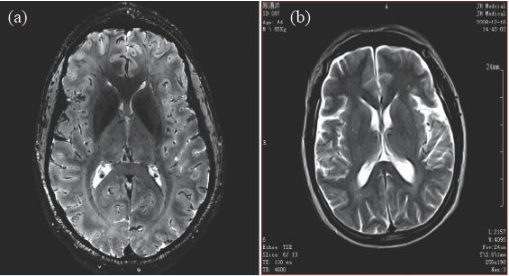

因此,磁共振成像技術(shù)目前的發(fā)展趨勢(shì),是朝著更高磁場(chǎng)強(qiáng)度發(fā)展,以期獲得更高分辨率的圖像,并實(shí)現(xiàn)多核成像。圖6 顯示了磁場(chǎng)強(qiáng)度的高低對(duì)圖像分辨率的影像,(a)為7 T 磁場(chǎng)下的圖像,(b)為0.35 T磁場(chǎng)下的圖像,二者的圖像分辨率可見(jiàn)一斑。

圖6 T2 加權(quán)成像(a)7 T 下的成像,分辨率約0.3 mm;(b)0.35 T下的成像,分辨率約1 mm